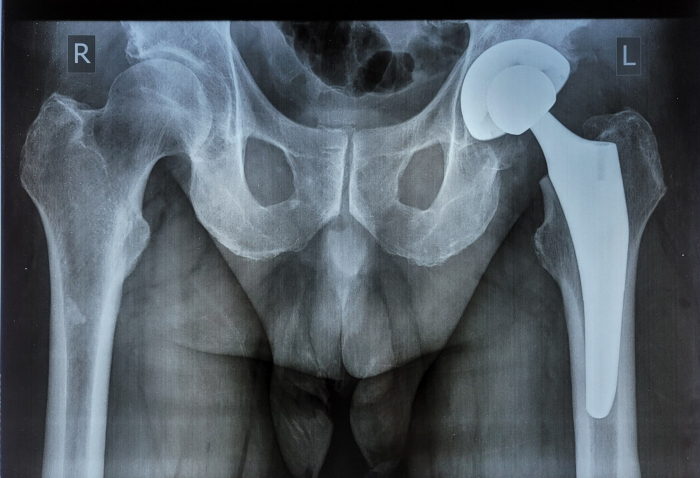

У Закарпатській обласній лікарні проводять безкоштовне ендопротезування кульшових суглобів

Такі операції проводяться згідно з державною програмою всім потребуючим, у першу чергу жителям Закарпатської області і переселенцям, а медзаклад забезпечений безкоштовними імплантами безцементного та цементного типу фіксації для проведення первинного ендопротезування. Ендопротезування кульшового суглоба — це оперативне втручання, при якому проводиться заміна ураженого суглобу на штучний імплант, так званий ендопротез. Після заміни суглоба у пацієнта зникає біль та збільшується об’єм рухів у суглобі.

Зазвичай, суглоби замінюють людям у старшому віці, які відчувають сильний біль і практично не можуть ходити, розповів завідувач відділення ортопедії та травматології Іван Дорогій. Тривалість оперативного втручання залежить від складності випадку і в середньому складає 1,5-2 години. На реабілітацію в середньому потрібно 6-8 тижнів, в залежності від складності випадку і загального стану пацієнта.